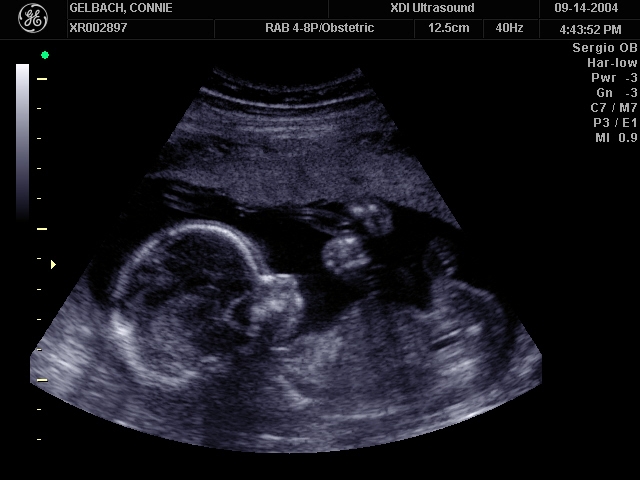

Sonograms